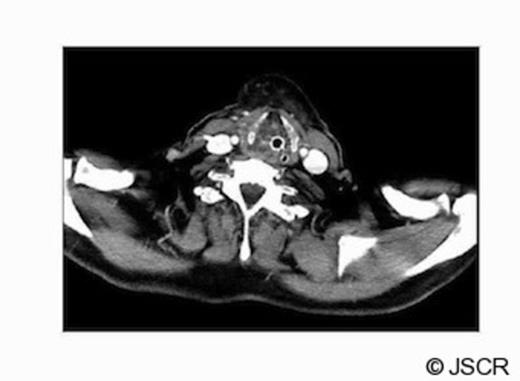

The contrast CT scan of the neck was performed on day 4 (Fig 1.), showing soft tissue oedema around the orotracheal tube, oropharynx and laryngopharynx extending from the posterior aspect of the hyoid bone down to the level of the thyroid cartilage. There was no fluid or pus collection.

The contrast CT scan of the neck performed on day 4; showing soft tissue oedema around the orotracheal tube, oropharynx and laryngopharynx